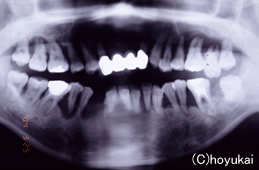

| 治療前の写真です。37歳女性、歯周病により下顎の前歯がグラグラした状態でした。レントゲンで見ると歯槽骨(顎の骨)が歯周病により大部分が吸収されているのが分かります。 |

抜歯と同時にインプラントを6本埋入しました。右図がインプラント埋入後のレントゲン写真です。 |